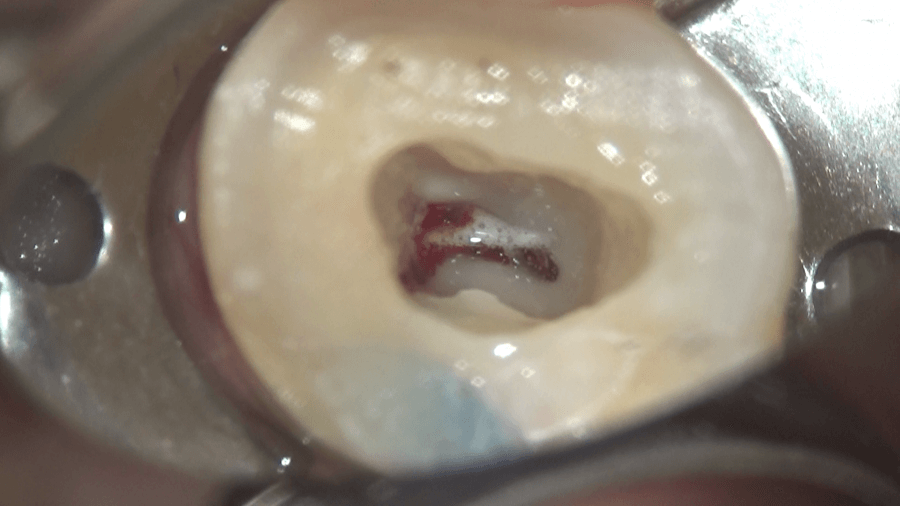

ニッケルチタンファイルを併用し、

4つの根管の入り口、専門用語で根管口を広げることができました。次回、根管の長さをはかり、大きくし、根の最終的な処置だある根管充填を行い、根管治療を完了させる予定です。

この行程、実は根管治療の中でも、もっとも重要なポイントの一つと言われています。入り口を的確に開けることにより、根管の処置をやりやすくできるのは、想像できるかと思います。